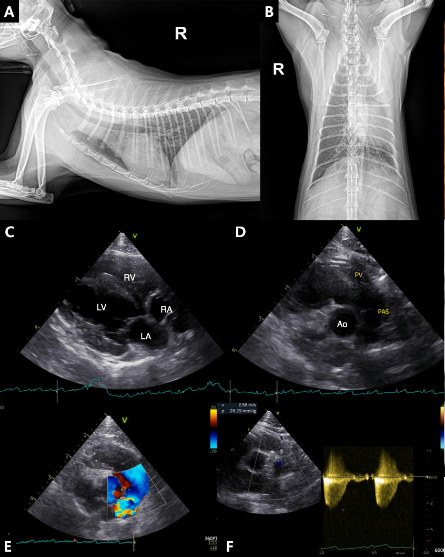

■ 편측성 폐동맥 협착증·폐동맥 형성부전증 고양이 ‘풍선 성형술’로 교정

세 번째 논문은 편측성 폐동맥 협착증과 반대편 폐동맥 형성부전증이라는 복합 심폐기형을 가진 4개월령 고양이에서 풍선 성형술로 치료한 후 장기 예후를 추적한 증례로 'Journal of Veterinary Medical Science(SCI)'에 게재됐다.

해당 환자는 4개월령 고양이로 심장 초음파에서 우측 폐동맥 가지의 폐색과 편측 폐동맥 무형성이 확인됐으며, 협착부 해소를 위한 풍선확장술을 실시했다. 시술 후 압력경사는 31.19 mmHg (velocity: 2.79 m/s)로 감소했으며, 1년 후 재검에서는 우심실의 비대 및 우심방 확장 소견도 개선되어 심장이 정상화 됐다.

해당 환자는 추적 관찰된 3년간 무증상으로 투약 없이 지내고 있다. 해당 연구는 드문 선천성 심폐기형에 대한 성공적인 인터벤션 치료와 장기 예후를 제시한 사례로, 향후 유사 질환 치료에 중요한 참고자료가 될 것으로 기대된다.